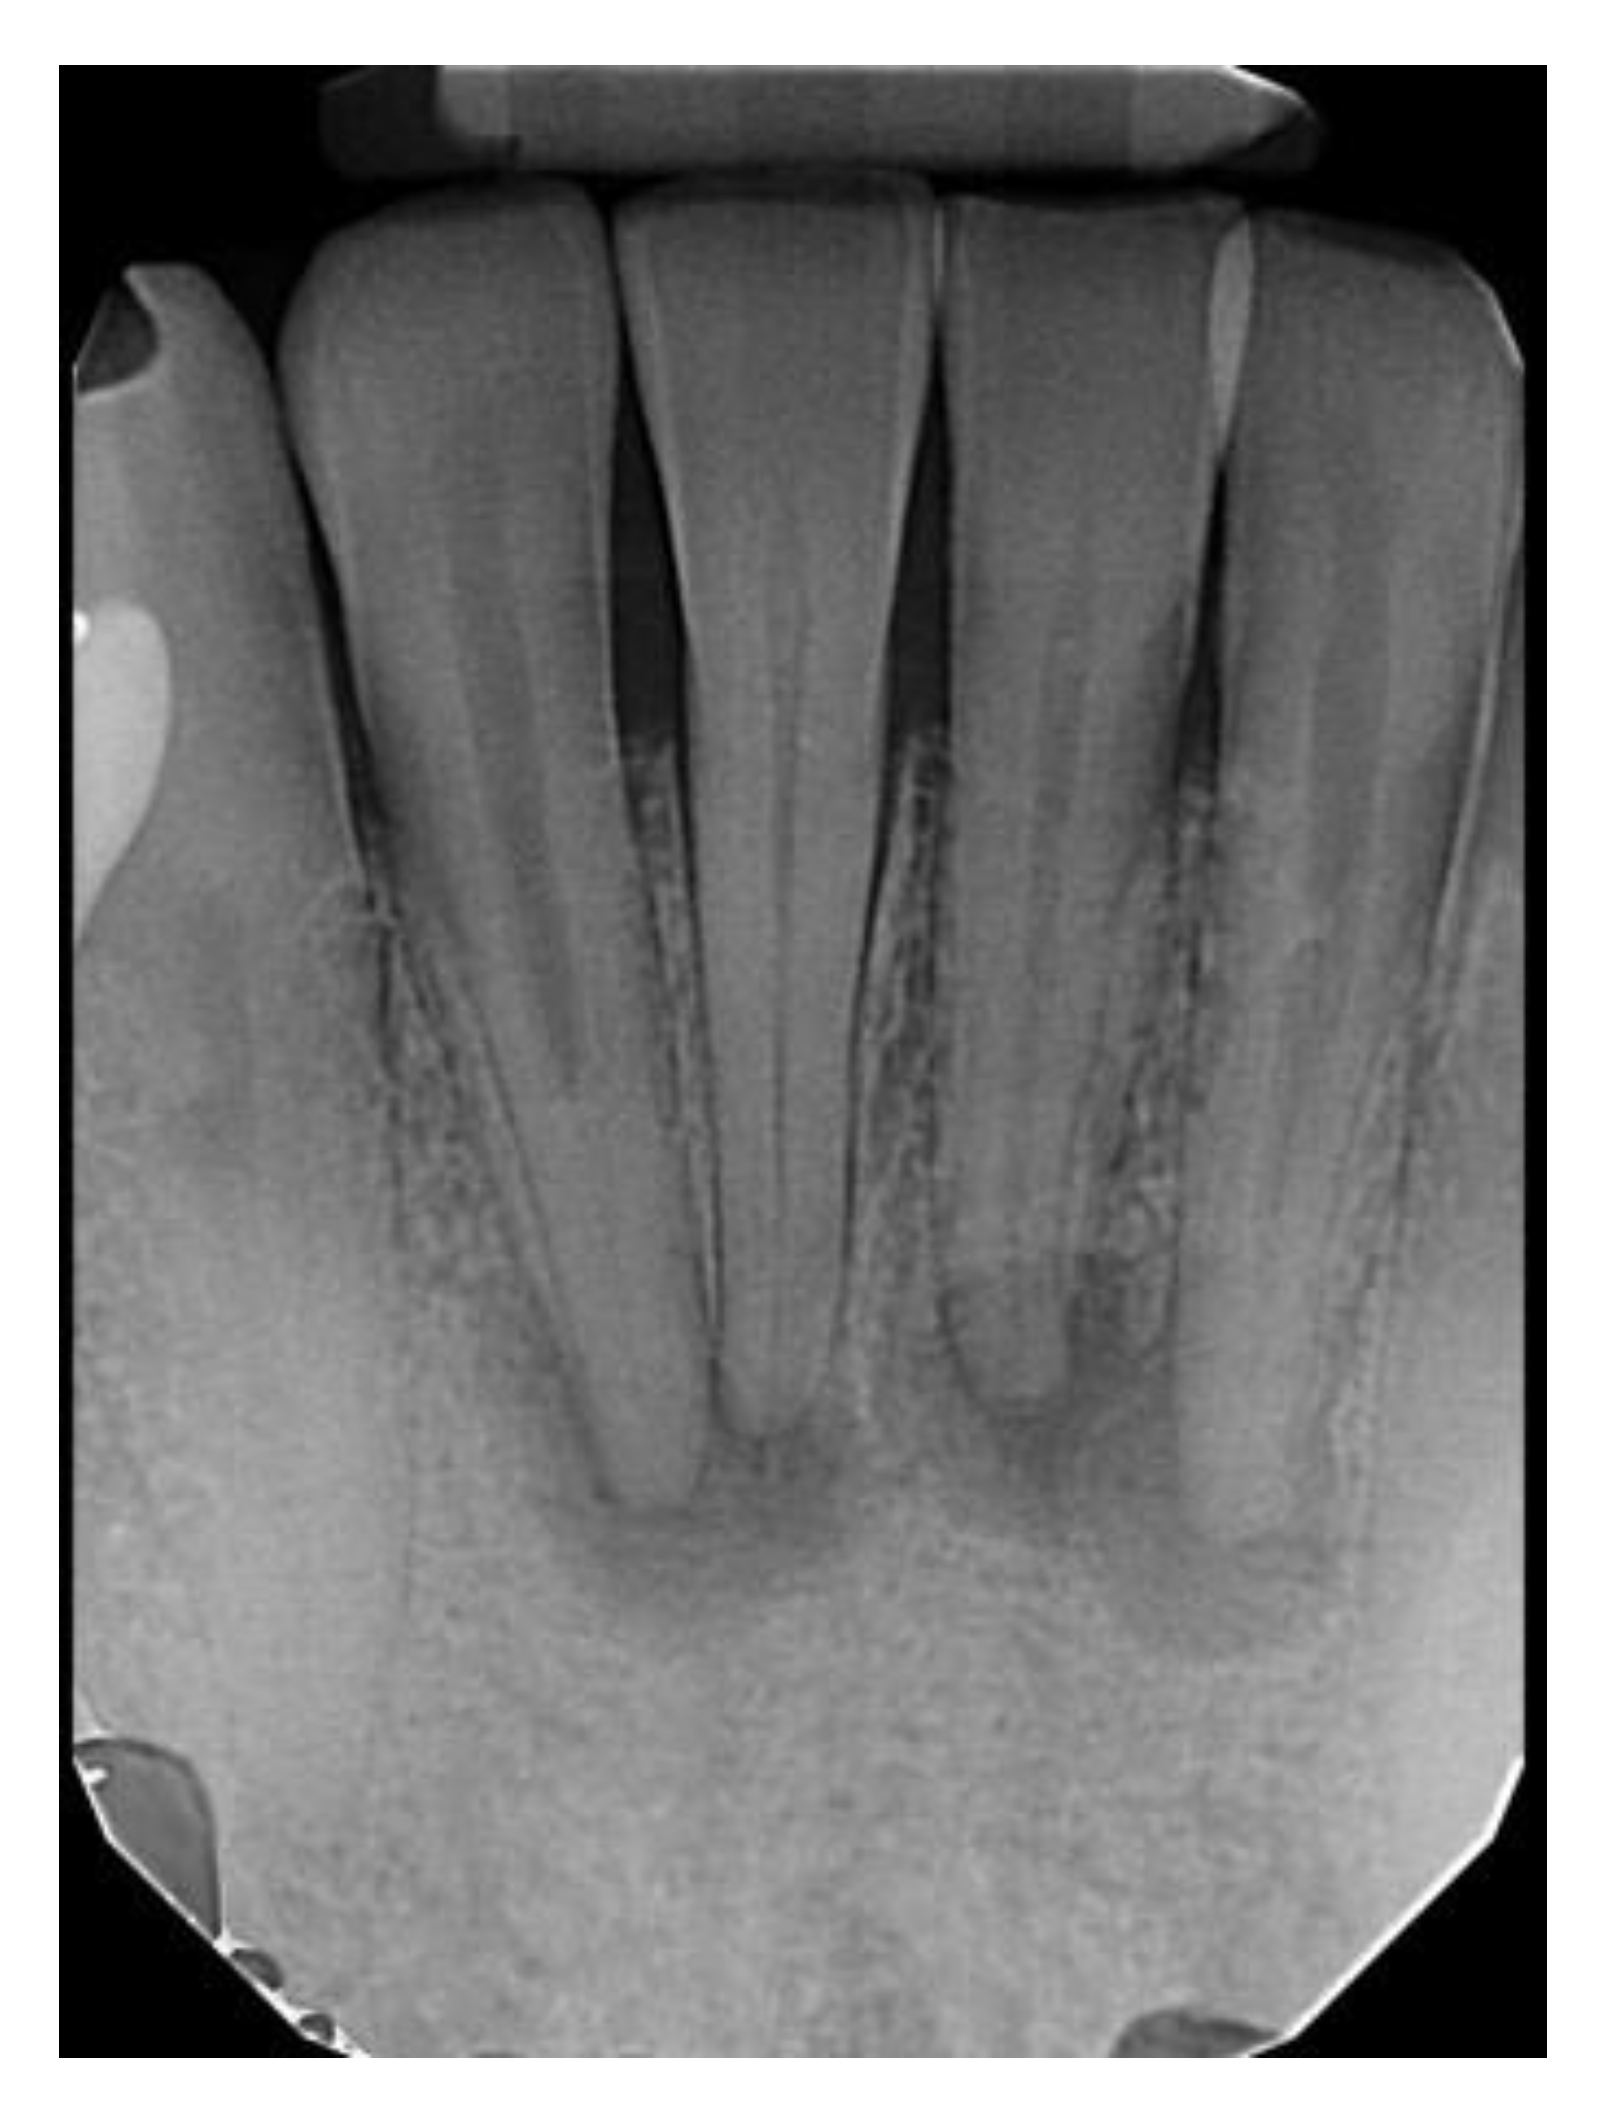

Types of COD